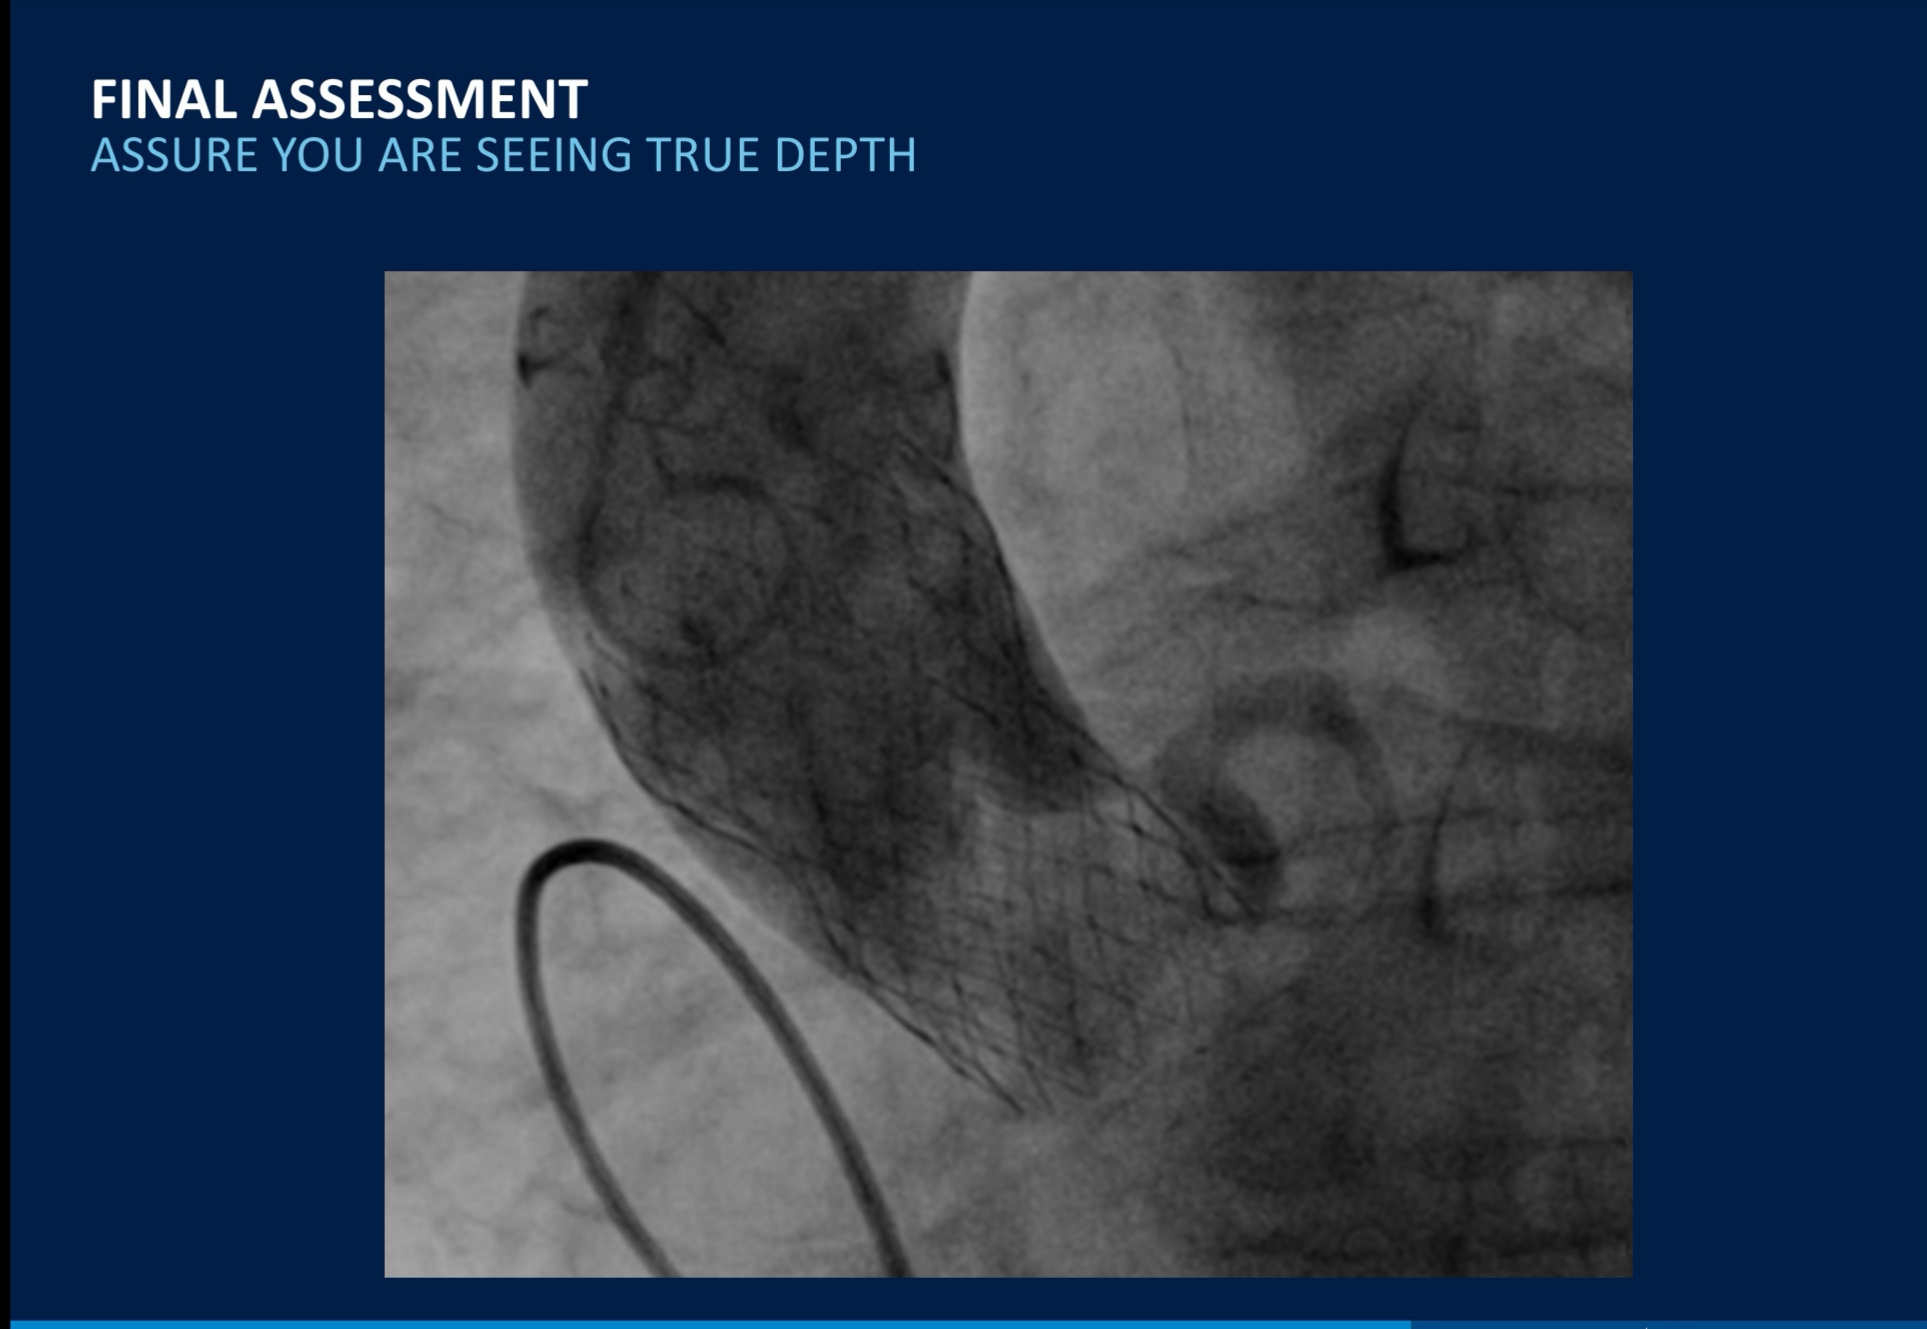

Esso può essere eseguito “a cuore aperto” oppure con la TAVI (Transcatheter Aortic Valve Implantation).

L’impianto percutaneo della valvola aortica (TAVI) può essere considerato come un’alternativa all’intervento di sostituzione valvolare chirurgico tradizionale in caso di controindicazione e/o alto rischio chirurgico se tale approccio è di pari efficacia clinica e presenta un rischio più basso

Dal maggio 2016, dopo relativa certificazione al montaggio della valvola, ho partecipato attivamente a 81 come montaggio, dove abbiamo potuto evidenziare che la principale complicanza è dovuta alla artero/atero sclerosi delle arterie femorali.

Questo crea difficoltà sia sel momento di inserzione della valvola montata sul proprio delivery che per la chiusura dell’accesso con i sistemi a “Proglide”, dando origine a sanguinamento o formazione di ematomi nella zona femorale in rari casi!